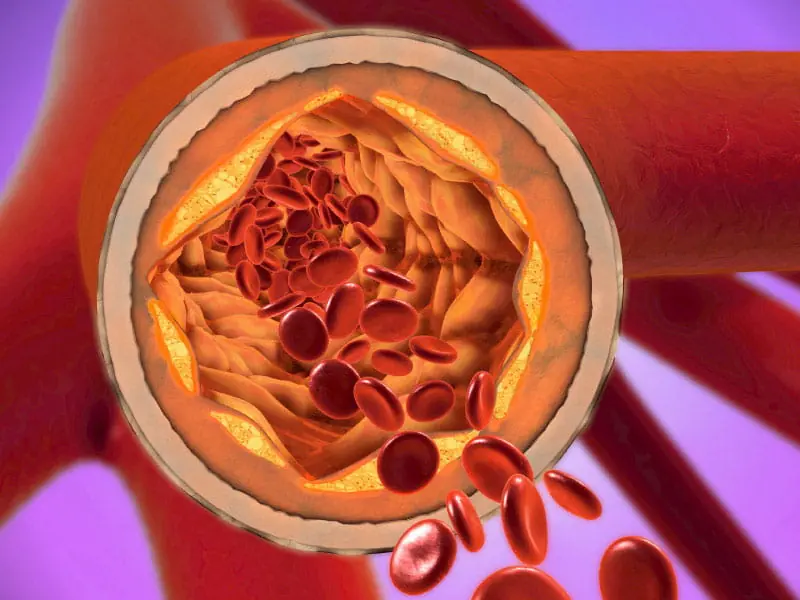

Doctors Warn: These 3 Morning Habits Can Worsen High Blo.od Pressure and Cholesterol

Your Morning Routine Might Be Raising Your Blood Pressure